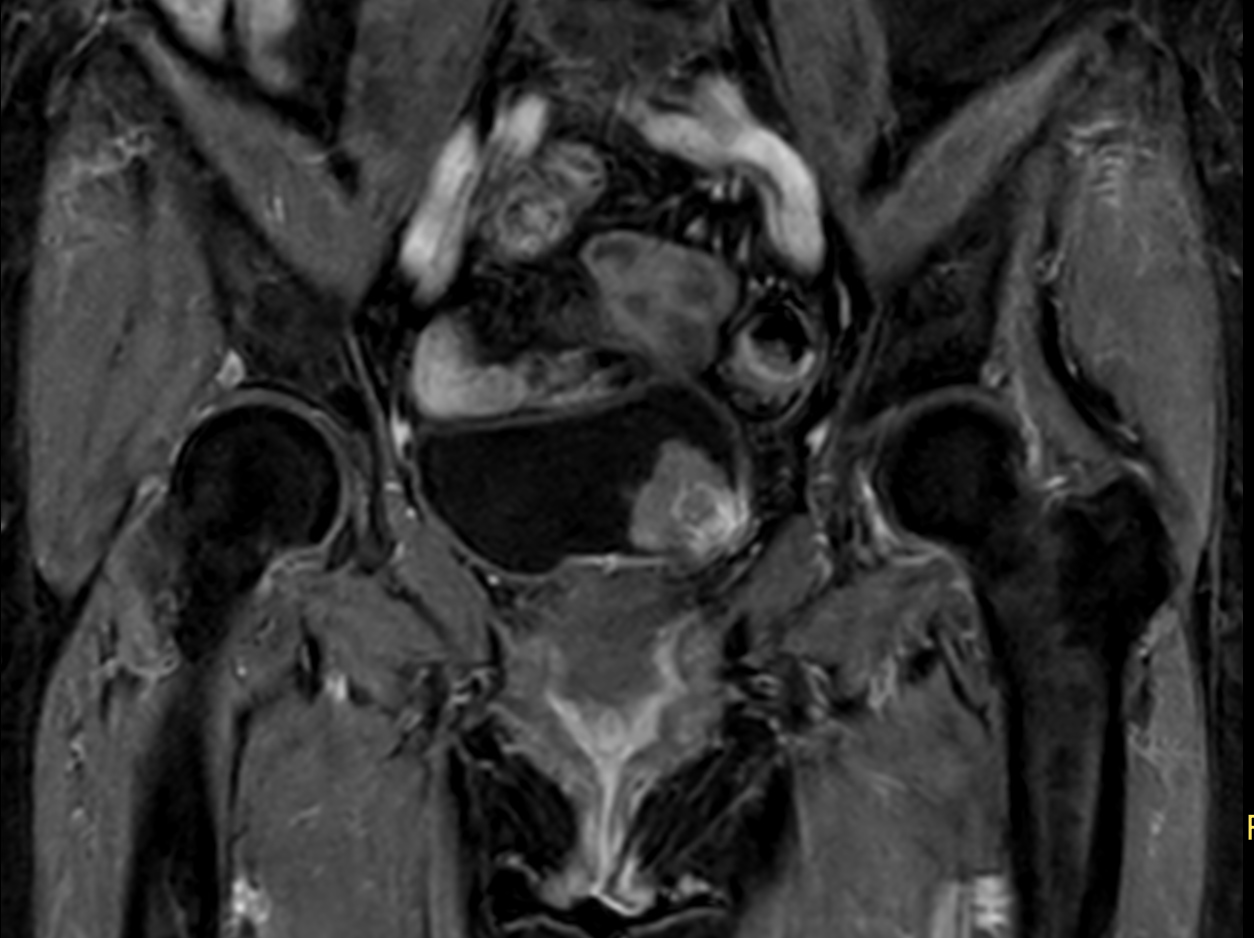

Patient with bladder cancer. The ExamCard includes techniques for motion reduced imaging (MultiVane XD), 3D TSE imaging (PelvisVIEW) allowing for multiple image directions in one single scan, a multi-phase contrast-enhanced sequence (4D FreeBreathing) to improve imaging confidence and Compressed SENSE to accelerate the entire exam.

T2w TSE MultiVane XD